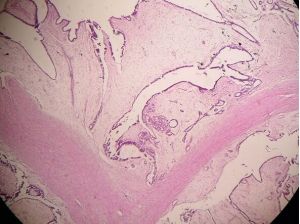

乳腺纖維腺瘤組織切片臨床表現

3.乳腺病灶活檢

根據病史、體檢或影像學檢查難以鑑別的乳腺腫塊,可採取穿刺或手術切除的方法,進行組織病理學檢查,明確診斷。